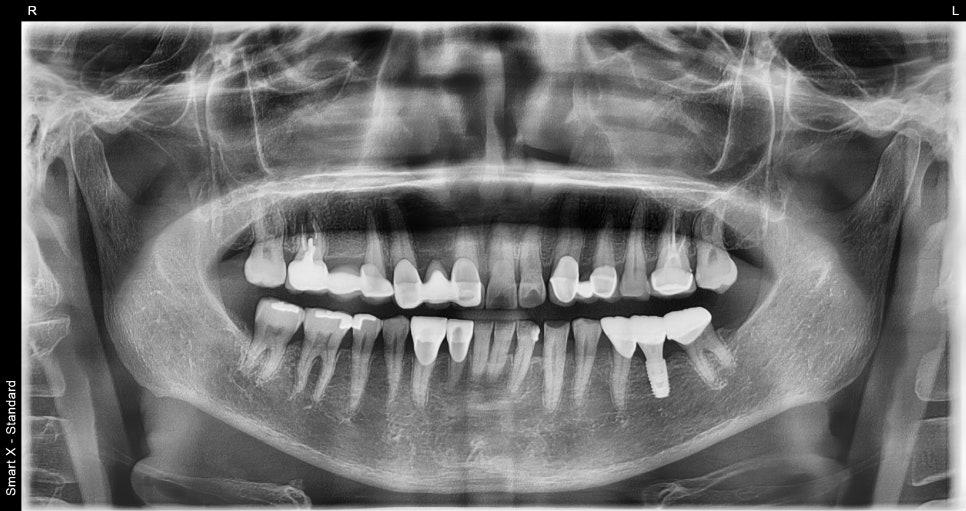

처음 내원 하셨을 때 파노라마 X-ray

임플란트 수술 직후 촬영한 X-ray입니다.

수술 직후 파노라마 X-ray

최종 파노라마 X-ray